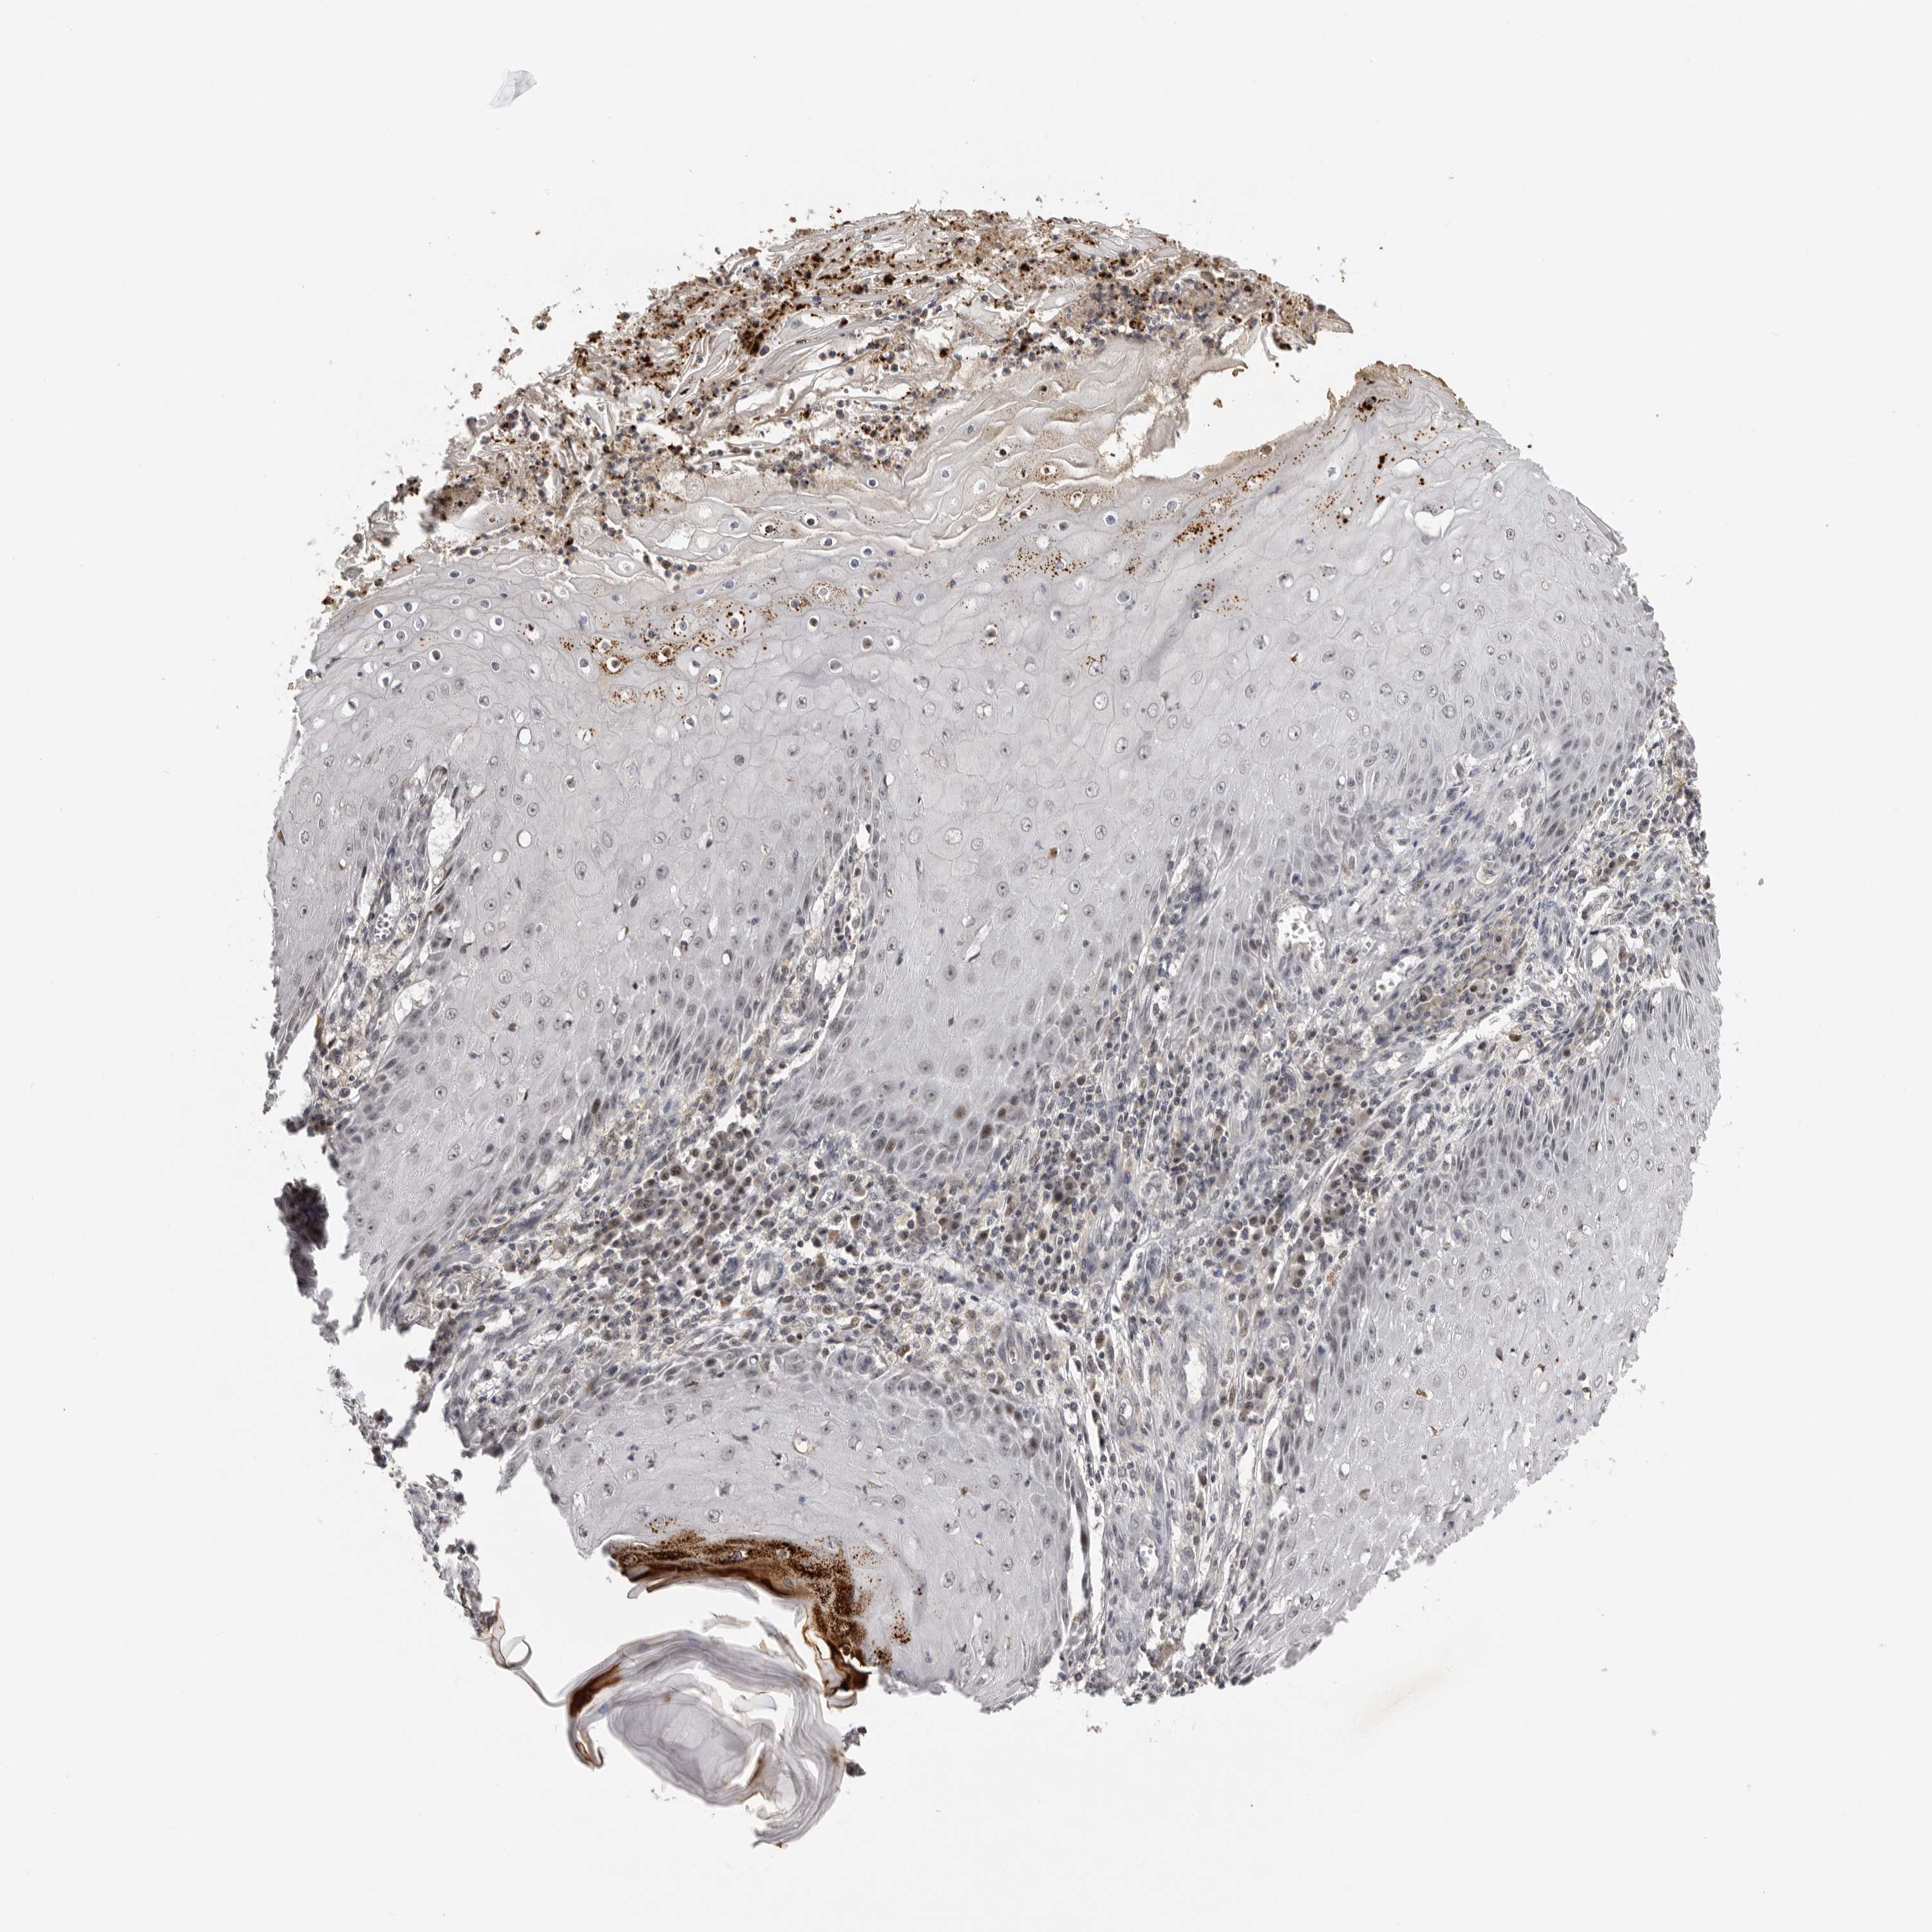

Basal cell and squamous cell cancer

SKIN CANCER - Protein expressioni

A mouse-over function shows sample information and annotation data. Click on an image to view it in a full screen mode. Samples can be filtered based on level of antibody staining by selecting one or several of the following categories: high, medium, low and not detected. The assay and annotation is described here.

Each image is clickable and will lead to virtual microscopy that enables deeper exploration of all samples and also displays staining intensity scores, fraction scores and subcellular localization as well as patient and tissue information for each sample.

Antibody HPA023103

Squamous cell carcinoma, NOS